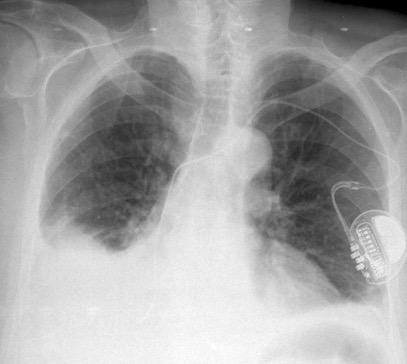

Síndrome de afectación postcardiaca (postcardiac injury)

Post infarto 1-7 % (Dressler)

Trauma cerrado Implantación marcapasos

Cirugía cardiaca. 17-31% (Post.pericardiotomía)

3707 pacientes 29 Derrames (0,78%) > de 25% del hemitórax

Todas menos 2 Izdos.

Angioplastia

By-pass coronario 21-10-03